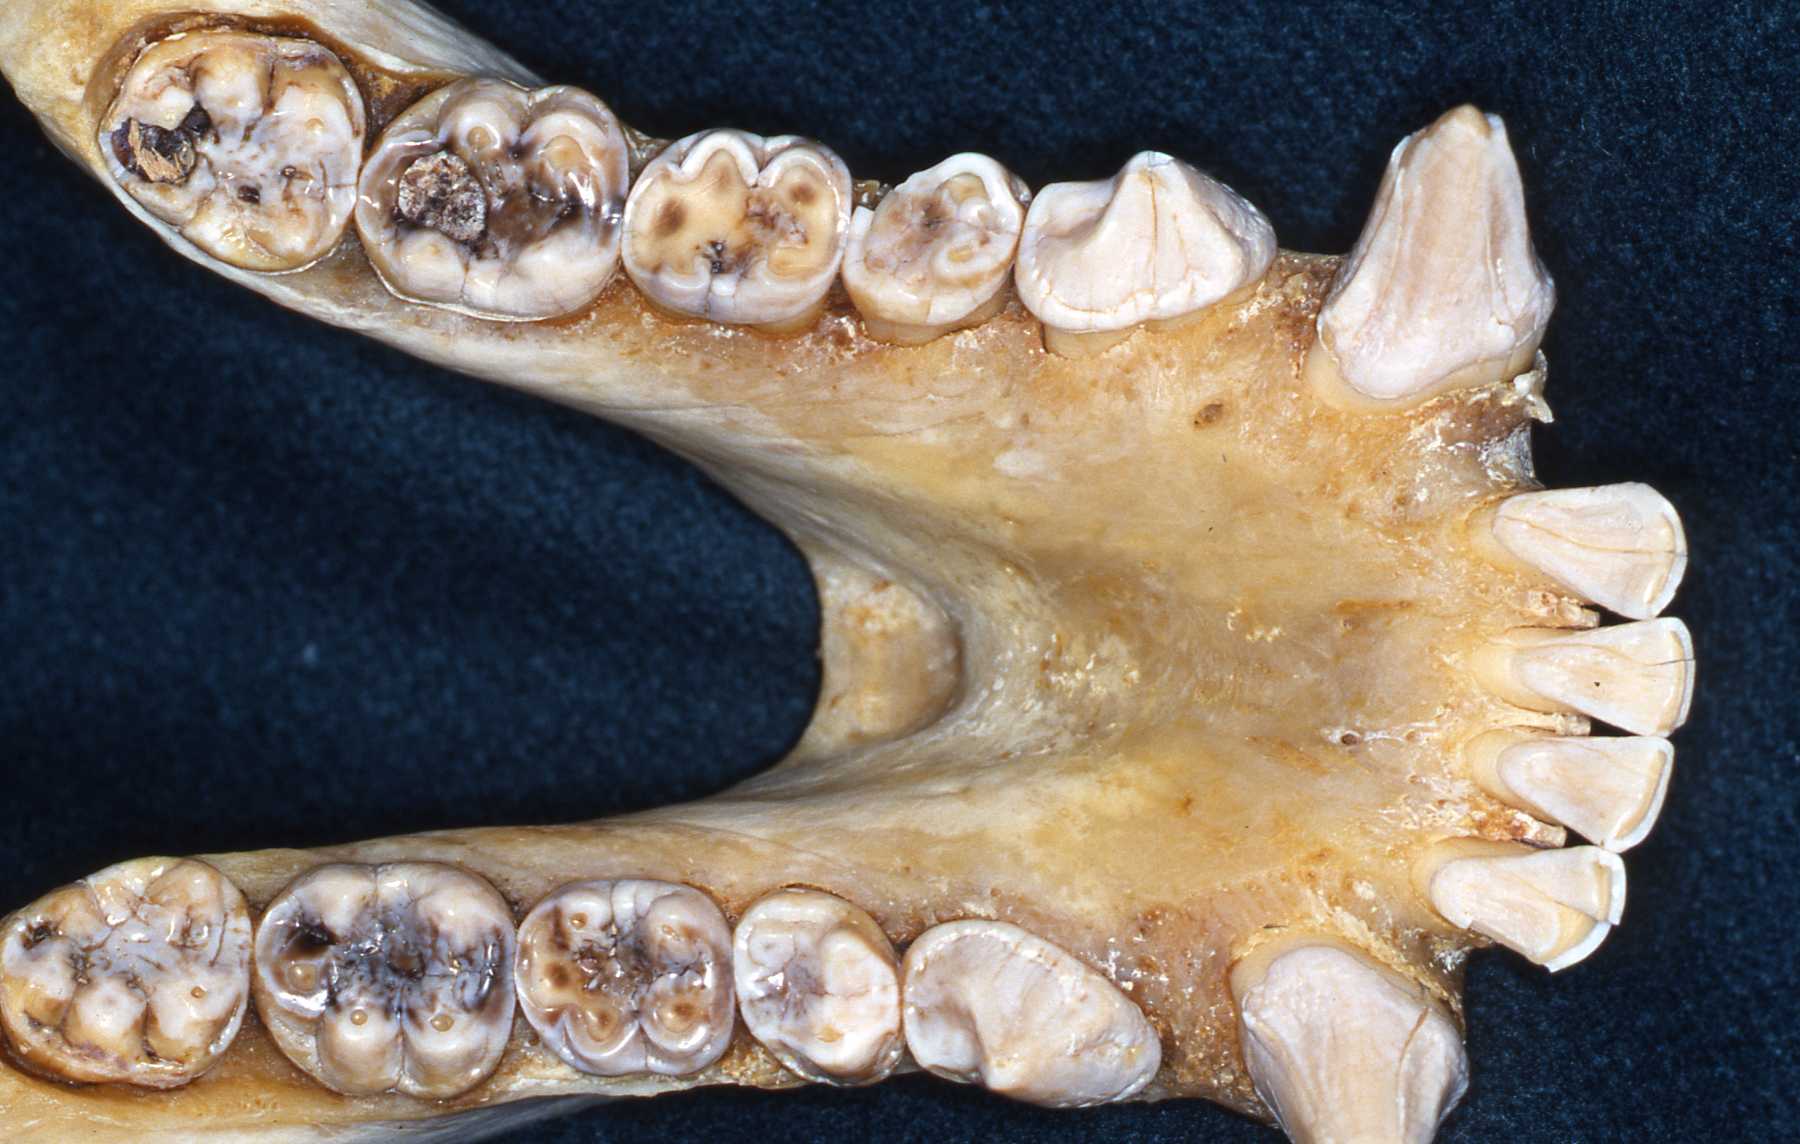

Dentists will recognize the primate dentition gross anatomy as similar to their human patients. Veterinary dentists will have to do some preparation to become familiar with it. The specific anatomical variations of the coronal portions of the teeth of the various species are only of modest treatment concern. However, the anatomical variations of root configurations are more significant. These should be reviewed whenever possible to prepare for extraction or endodontic treatments. The types of pathosis encountered will be fundamentally the same as in other mammals.

The apes will have the same number of teeth as humans. That is 20 primary teeth and 32 permanent teeth. The same is true for the old world monkeys. Some new world monkeys have three premolars per quadrant. Other primate groups have various dental formulae. The primate teeth are anelodont with very few exceptions (aye-aye for example). There are also variations in numbers of roots. Therefore, again, preoperative radiographs should always be reviewed prior to extraction or endodontic procedures. The root apices usually have single orifices with a small percentage having auxiliary canal openings or perhaps two apical openings as often found in humans.

Enamel erosion throughout dentition due to chronic regurgitation/ingestion behavior

I frequently encountered caries in many animal groups when I began serving as a consultant. Until the early 1980s comprehensive veterinary care was not commonly provided in zoos, so physical and cursory oral and dental exams were only done when significant problems were already present. Proper diets had not been researched and keepers often provided their charges with sweet treats that led to tooth decay. Fortunately, zoo diets are scientifically developed now and keepers know to not provide improper treats.

I have also encountered significant dental attrition due to bruxism in many primate species. The psychological stress of confinement certainly contributes to such habits. Again, zoo keepers are very aware of such issues and these are addressed in many effective ways. Another habit related to stress, regurgitation of food and reingesting it, causes very significant damage to the entire periodontium, leading to loss of teeth. See Dr. John Huffs' on treating Tino at Salt Lake City zoo. I examined Tino when he was young at our zoo. He already had the regurgitation habit then.